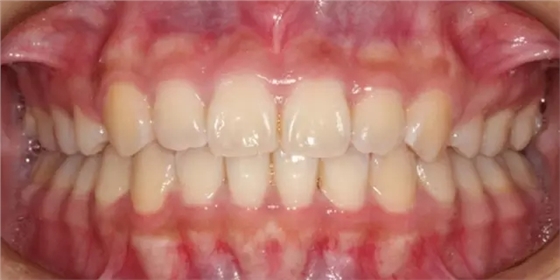

上下牙列擁擠,磨牙尖牙Ⅱ 類關(guān)系,3 度的深覆牙合,上頜中切牙伸長內(nèi)傾拔除上頜雙側(cè)的第一前磨牙,先粘上頜高轉(zhuǎn)矩的自鎖托槽排齊牙列,唇向開展上頜切牙,有一定的覆蓋,粘下頜標準轉(zhuǎn)矩托槽,上頜 1, 2 之間植入種植支抗壓入,同時后牙 5, 6 之間植入種植支抗內(nèi)收前牙,打開咬合關(guān)閉間隙。治療關(guān)鍵:前牙轉(zhuǎn)矩的控制第 1 個月 上頜粘上 Damon Q 高轉(zhuǎn)矩托槽,上 .014 熱激活 NiTi 絲。第 3 個月 上換 .014 x .025 熱激活 NiTi 絲。第 5 個月 上頜基本排齊,覆蓋增大,上換 .017 x .025 NiTi絲,下頜粘托槽,下 .014 熱激活 NiTi 絲。第 7 個月 上 .017 x .025 NiTi 絲加搖椅,下?lián)Q .014 x .025 熱激活 NiTi 絲第 9 個月 上頜換 .019 x .025 NiTi 絲加搖椅,下頜換 .017 x .025 NiTi 絲第 11 個月 下頜換 .019 x .025 加搖椅,上頜 1, 2 之間, 5, 6 之間植入種植釘,下頜出現(xiàn)散隙。第 13 個月 上頜換 .019 x .025ss 加搖椅,前牙種植釘用 Power Chain 壓低前牙(每側(cè) 100g),后牙種植釘關(guān)閉間隙(每側(cè) 150g),下?lián)Q .019 x .025ss,Power Chain 關(guān)閉間隙。第 19 個月 上頜前牙基本壓低到位去除前牙種植釘,繼續(xù)用關(guān)閉間隙,下頜散隙關(guān)閉。

第 22 個月 上頜覆蓋變小,去除 5, 6 之間種植釘,后牙前移關(guān)閉間隙。第 30 個月 患者未配合中線牽引,下中線仍有 1mm 右偏,患者對矯治效果滿意要求拆除,拆除固定矯治器,取模制作壓模保持器。 1.骨性 Ⅱ 類的患者內(nèi)收前牙時需對上頜前牙的轉(zhuǎn)矩進行較好的控制才能獲得良好的面型和唇部形態(tài)。 2.露齦笑的患者治療前要分析其病因是唇、牙齦、牙齒、牙槽骨、上頜骨或多種因素結(jié)合,再制定矯治方案。 3.Ⅱ 類第二分類伴露齦笑的患者的上頜前牙移動軌跡是唇向開展-壓低-整體內(nèi)收。 4.Ⅱ 類第二分類牙齒舌傾比較厲害的情況,上頜中切牙慎用樹脂咬合墊。 5.壓低前牙或控根移動時容易發(fā)生牙根的吸收,需輕力緩慢的移動。